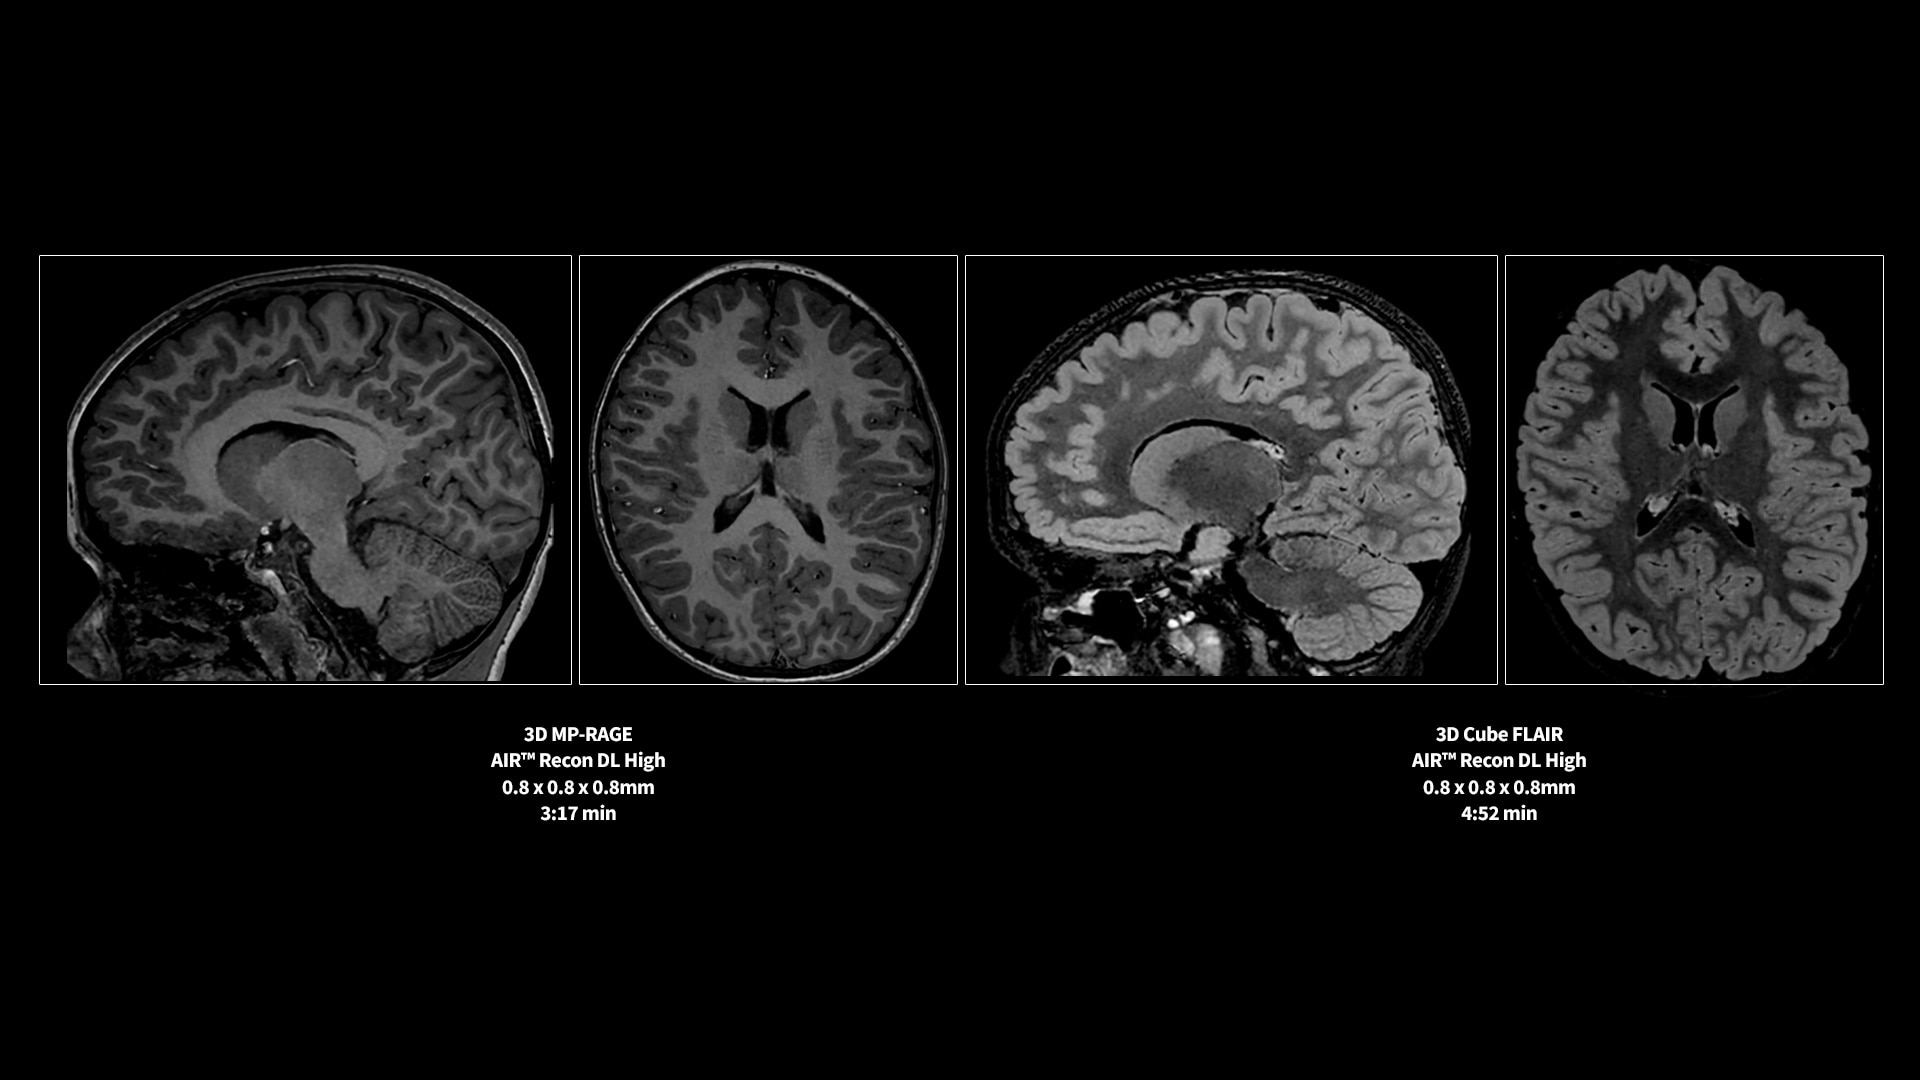

MR image reconstruction with AIR™ Recon DL

AIR™ Recon DL has revolutionized MR imaging with deep-learning based image reconstruction increased image quality, reduced scan time and improved SNR.